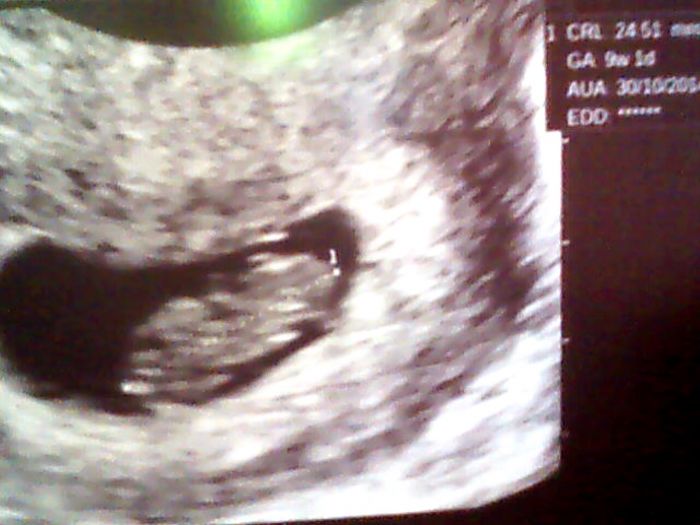

Dobré ráno holky,tak já hned ráno letěla na gyndu,včera večer jak jsem lezla z vany mi podjela noha a pěkně jsem sebou práskla do vany,bolel mě celý spodek,ale naštěstí jsem nekrvácela,ale tím,že mě ráno vzbudila bolest podbříšku raději jsem si zašla jelikož je víkend tak at nikde nelítám po pohotovosti.No naštěstí je vše v pořádku,mimi už má 2,4 cm ,dokonce se hýbalo

,tak se nám ulevilo.

no roste to za 9 dnů skoro 1 cm